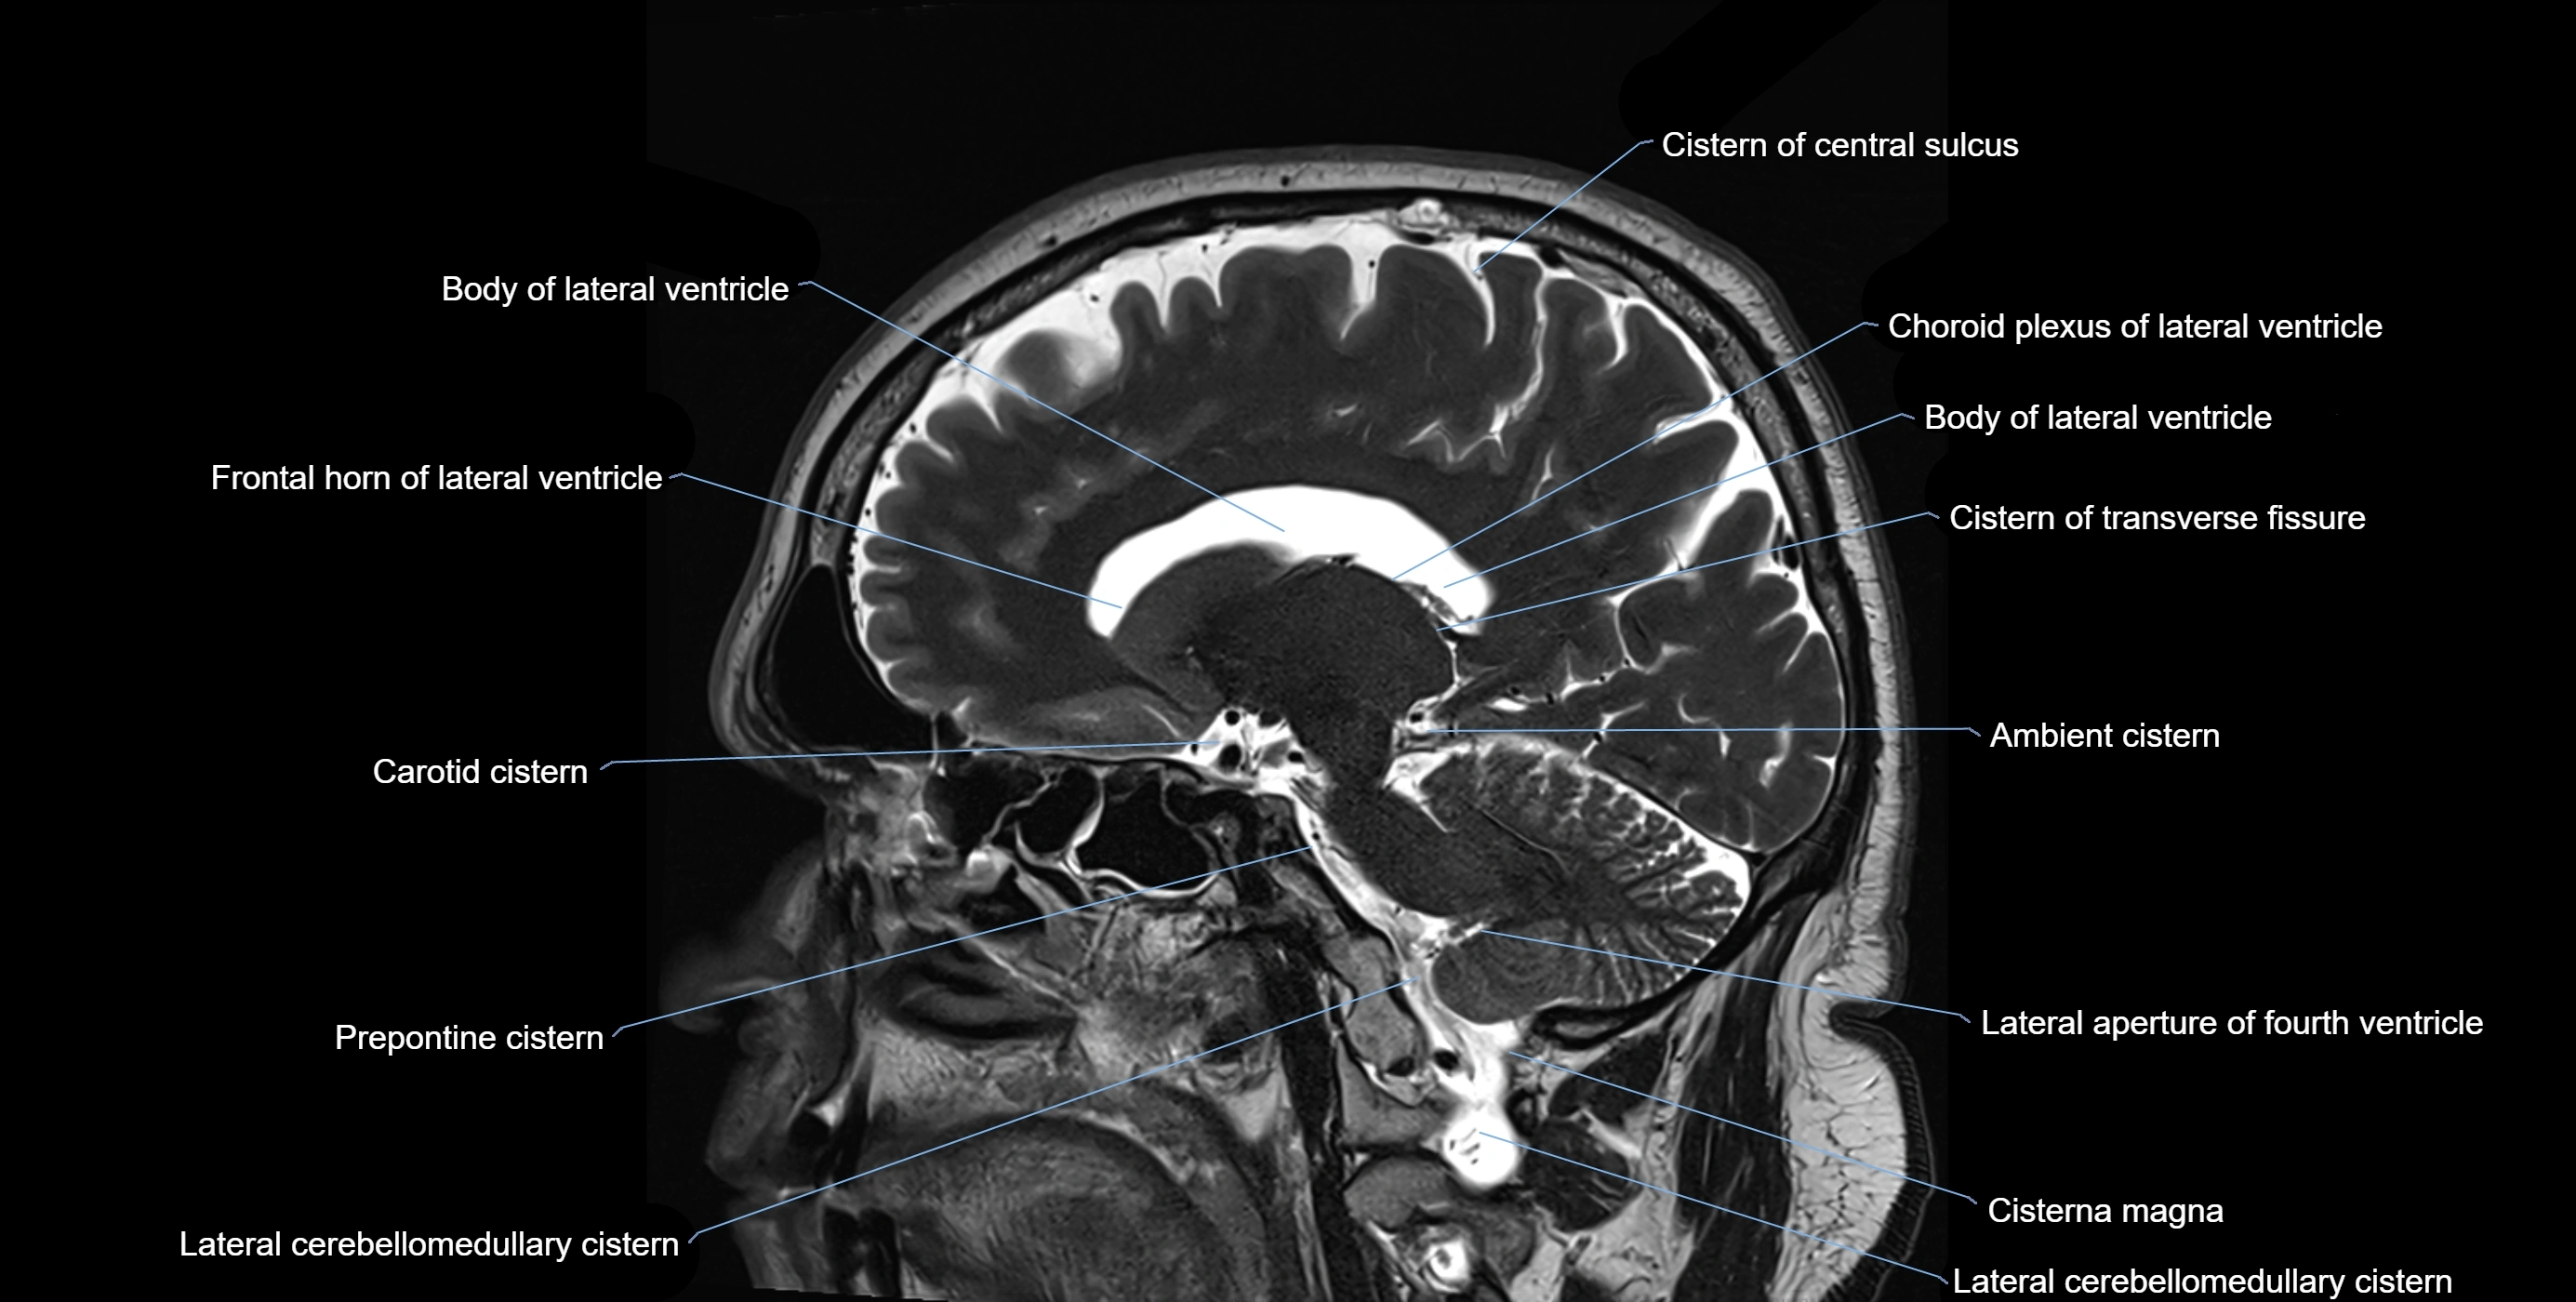

The ambient cistern is a paired, narrow, and elongated subarachnoid space located bilaterally along the lateral aspect of the midbrain. It serves as a conduit between the interpeduncular cistern anteriorly and the quadrigeminal cistern posteriorly. This cistern houses critical neurovascular structures, including parts of the posterior cerebral artery, superior cerebellar artery, trochlear nerve (cranial nerve IV), and the basal vein of Rosenthal. It plays an important role in the circulation of cerebrospinal fluid (CSF) and provides an anatomical corridor for various vessels and nerves passing around the midbrain.

MRI Appearance

• T1-weighted images:

• The ambient cistern appears as a region of low signal intensity, matching the dark appearance of CSF.

• Neurovascular structures within the cistern may appear as flow voids (signal loss from flowing blood) or as small dark linear structures.

• T2-weighted images:

• The cistern is hyperintense (bright) due to the high water content of CSF.

• Encapsulated vessels and nerves are seen as flow voids or hypointense lines within the bright background.